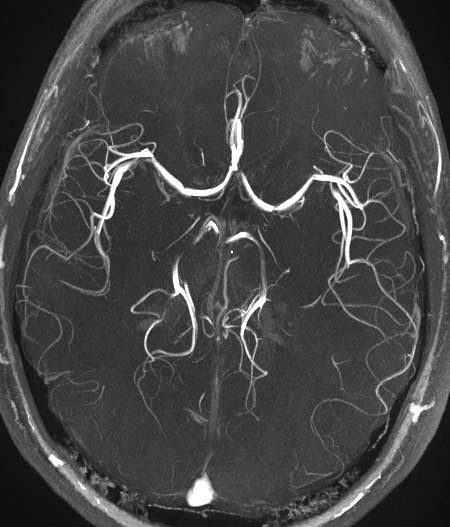

Det finns jättemånga häftiga så kallade pulssekvenser, där man använder en serie av olika typer av pulser, och avläsningsscheman. Man kan ta bilder av blodflöden, och man kan studera hjärnaktivitet.

MR-angiografi ser häftigt ut (bild på blodkärlen, obs inte min hjärna), se bild nedan: